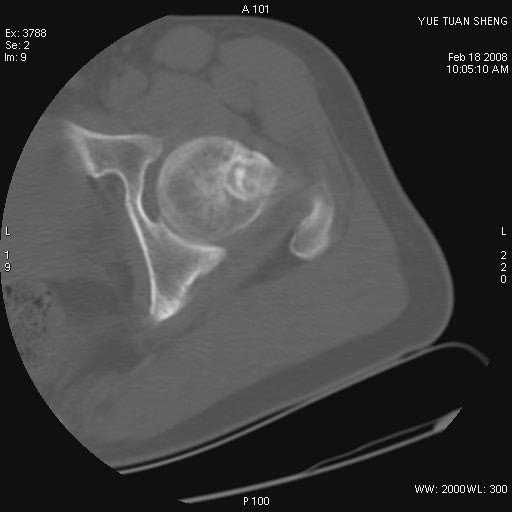

患者,男,56岁,左髋部疼痛1个月,x线:左股骨头高密度影,性质待定,右侧正常。左髋ct如图

左股骨颈区椭圆形磨玻璃样影,边缘明显硬化环环绕,其内见斑点状类钙化高密度影考虑 良性骨病-----骨纤,骨化性纤维瘤,内生软骨瘤。